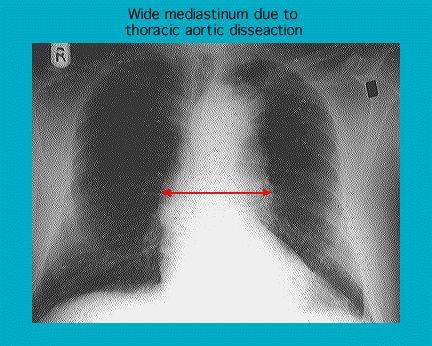

Radiografía que muestra la disección de la aorta torácica